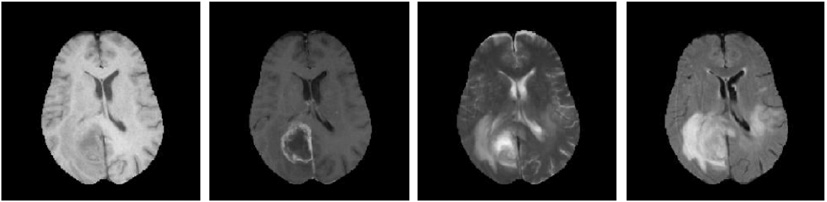

C3 -

A method for the vascular heterogeneity assessment of glioblastoma

The Hemodynamic Tissue Signature (HTS) method analyzes the perfusion MRI of a glioblastoma using an unsupervised learning approach to delineate four habitats within the lesion that exhibit different hemodynamic activity. The habitats describe the High Angiogenic Tumor (HAT) and Low Angiogenic Tumor (LAT) regions of the glioblastoma, and the potentially Infiltrated Peripheral Edema (IPE) and Vasogenic Peripheral Edema (VPE) of the lesion. Such approximation establishes a conceptual frame for the description of the tumor heterogeneity by means of the detection of clinically relevant sub-regions, a.k.a habitats, with differentiated imaging biomarkers. The preliminar results of this work were first presented in the conference contribution P4 (Juan-Albarracín et al, 2016) and it was finally published in the journal contribution P5 (Juan-Albarracín et al, 2018).